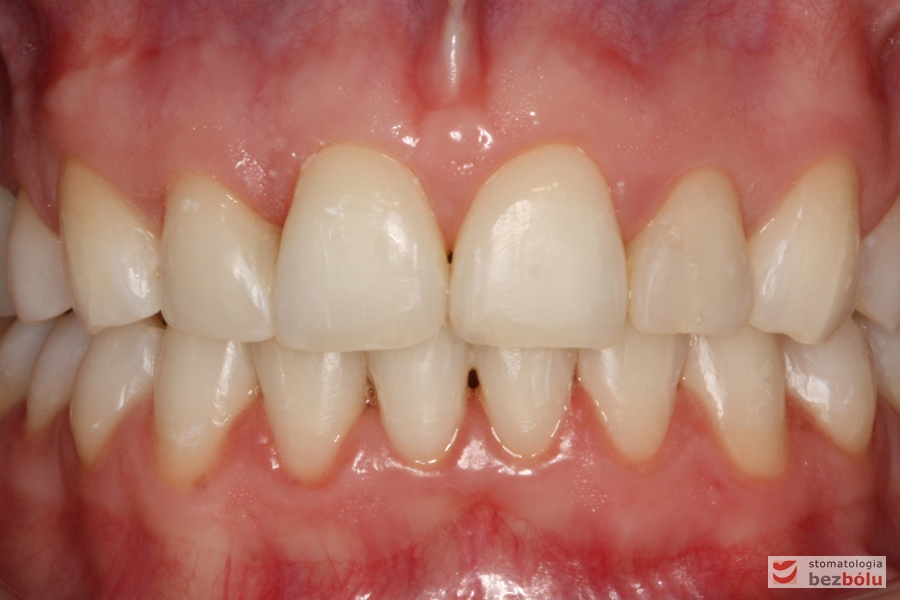

Młoda i urodziwa pacjentka (28 lat) zgłosiła się w celu korekcji wystającej i zrotowanej „jedynki” prawej górnej. Przeprowadzona diagnostyka wykazała: nieregularną linię dziąsła, proporcje zębów ~85%,spłaszczony łuk górny po stronie prawej z powodu zgryzu krzyżowego, ząb 11 poza łukiem w mezjorotacji, zaburzone proporcje siekaczy bocznych w stosunku do centralnych, starcie patologiczne na kle górnym po stronie prawej, rozbieżne osie długie w obrębie siekaczy i nieregularną linię dziąsła w obrębie stłoczonych siekaczy.

Diagnostyka – nieregularna linia dziąsła, proporcje zębów ~85%

Zaburzone proporcje siekaczy bocznych w stosunku do centralnych, starcie patologiczne na kle górnym po stronie prawej

Rozbieżne osie długie w obrębie siekaczy

Nieregularna linia dziąsła w obrębie stłoczonych siekaczy